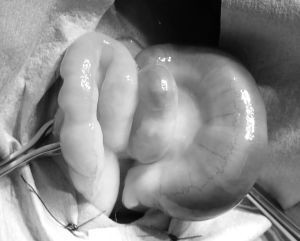

ウサギの子宮静脈瘤

今回は子宮疾患のウサギさんのご紹介です。

この子は子宮からの出血が止まらず、ヘマトクリット値(血液の濃さ)が9%まで低下(通常30~50%程度)。

年齢はまだ1歳3か月ほどでした。

ヘマトクリット値が10%を切るとかなり厳しい戦いになると言われている為、すぐに緊急手術を実施しました。

幸い、無事手術を乗り越えて元気になってくれました。

子宮は病理検査の結果、「子宮静脈瘤」との診断でした。